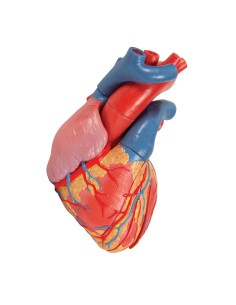

Dal cranio in 22 parti con incastri magnetici ai modelli di colonna vertebrale, da quelli di articolazioni a quelli di cuore, ogni pezzo della nostra collezione è progettato per un’immersione totale nello studio dell’anatomia umana. I nostri modelli, realizzati tramite scansioni di ossa vere, garantiscono un’esperienza tattile autentica e una fedeltà di peso quasi identica agli originali.